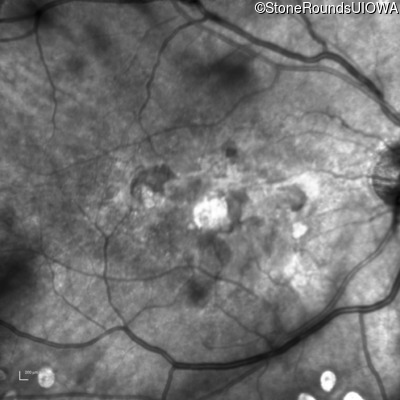

Malattia Leventinese (IIJ)

Malattia Leventinese (IIJ)

This 43 year old woman has experienced a gradual reduction in her central vision for the past 3 years.

| Malattia Leventinese | EFEMP1 | Arg345Trp CGG>TGG | AD |